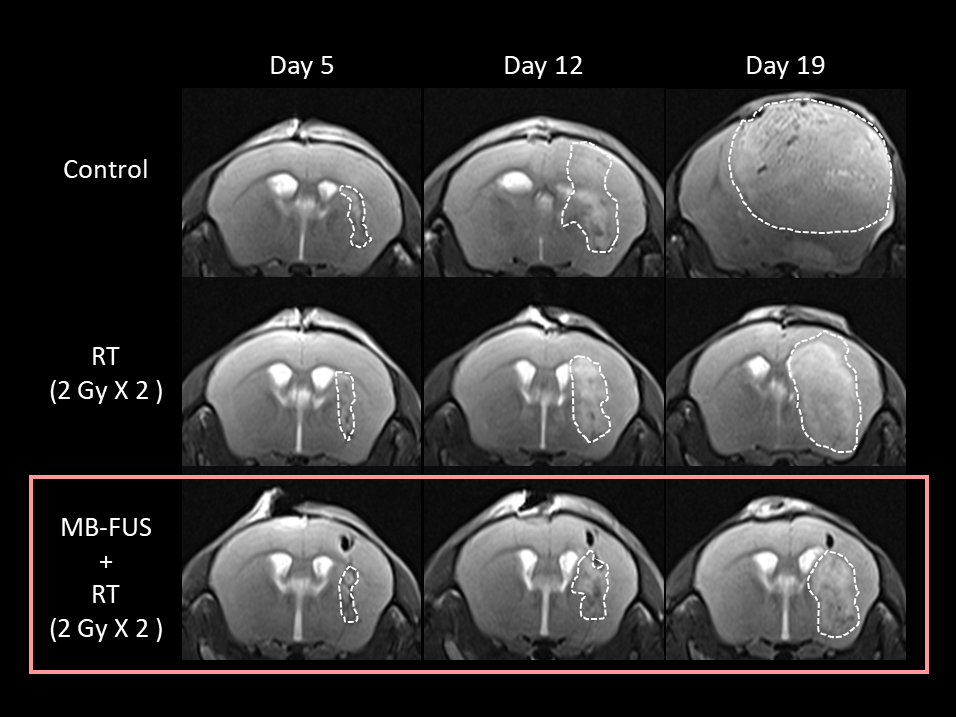

Radiotherapy is a standard-of-care therapy for these patients, but research suggests that reduced blood flow and oxygen concentration in the tumor area inhibits the efficacy of radiotherapy. NaviFUS has conducted preclinical studies that suggest disrupting the BBB using their focused ultrasound system significantly increases the oxygen content of brain tissue, which – when combined with radiotherapy – can increase the tumor-inhibiting effect of the therapy. Results of these studies were presented at the Foundation’s 7th International Symposium on Focused Ultrasound. The upcoming clinical trial aims to confirm these results in humans.